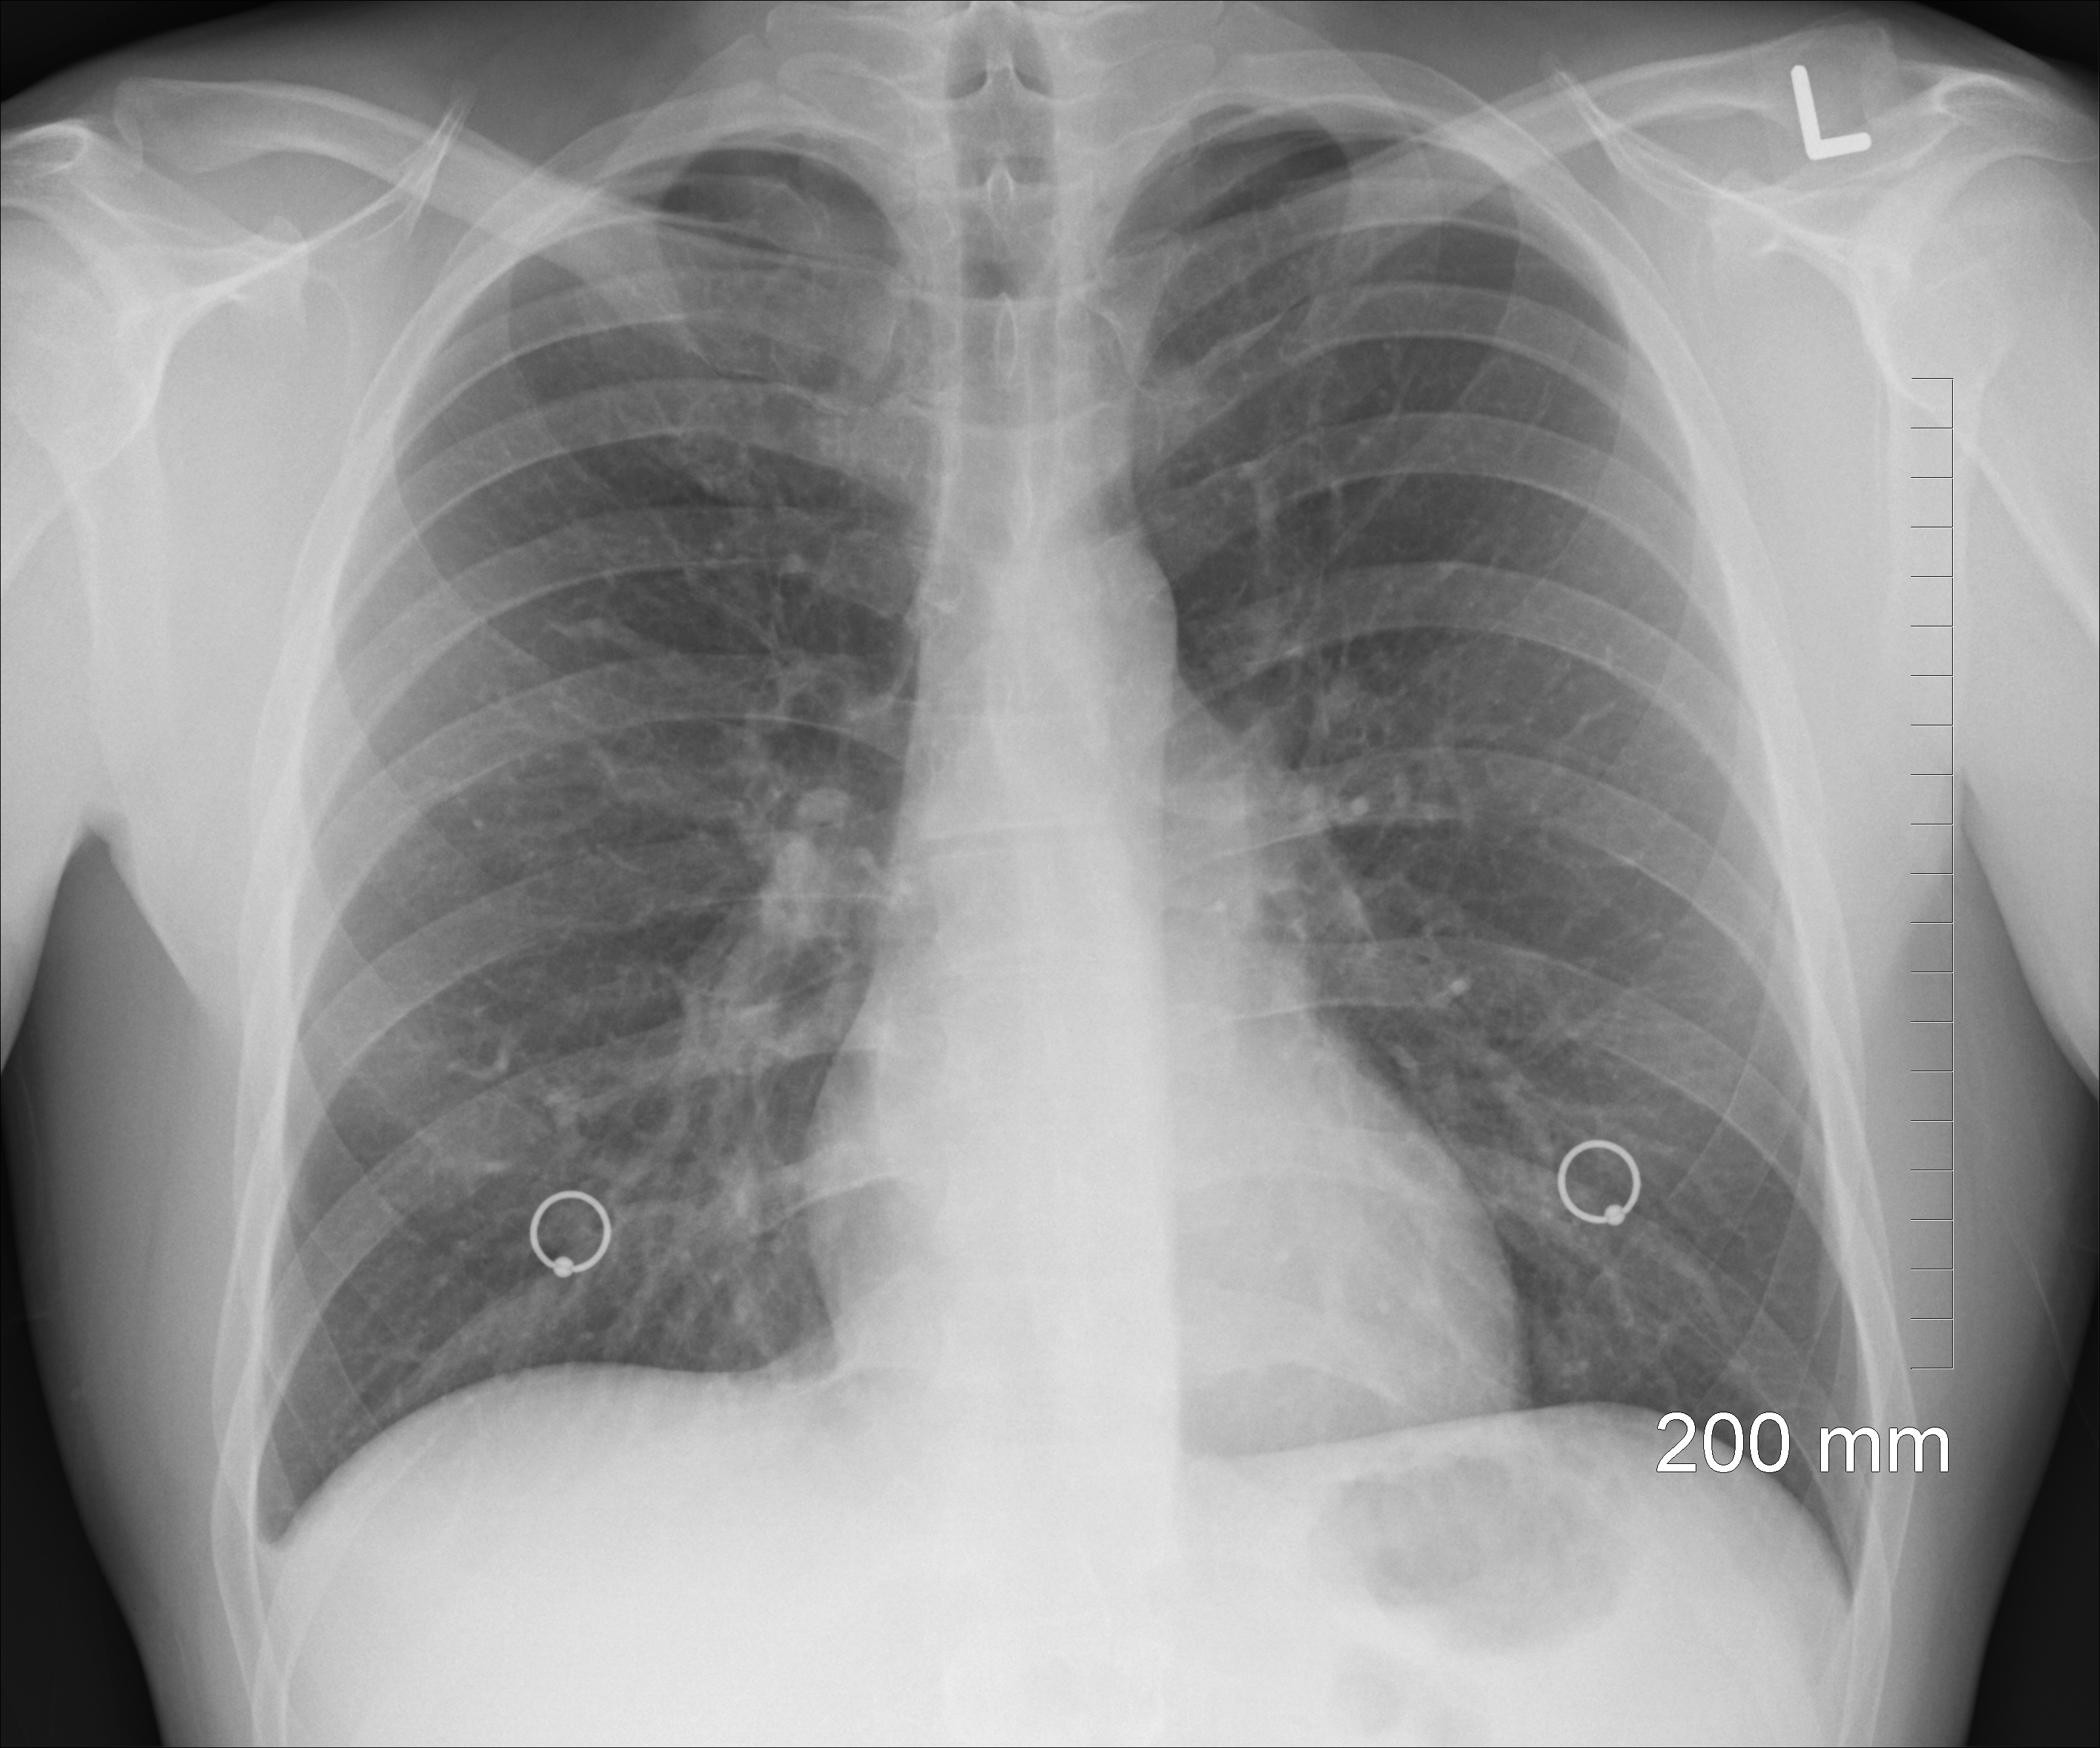

- Bardzo dużo jest takich pacjentów. We wszystkich poradniach pulmonologicznych są tłumy chorych. Lekarze mają zapełnione grafiki od rana do nocy. Zgłaszają się pacjenci z dusznościami. Robimy im badania radiologiczne klatki piersiowej i widzimy typowe zmiany wywołane wirusem SARS-CoV2. Nie wiemy jeszcze, dlaczego u niektórych pacjentów te zmiany są odwracalne, a u innych nie. Jesteśmy świadkami prawdziwych dramatów. Pamiętam 50- letnią chorą, która była wcześniej sprawną, zdrową osobą. Przed zachorowaniem na COVID miała prawidłowe zdjęcie radiologiczne klatki piersiowej. Po miesiącu od zachorowania, pomimo że otrzymała wszystkie możliwe leki, jej płuca są nieodwracalnie zniszczone, w taki sposób, że każdy ruch powoduje sinicę centralną. Wymaga ciągłego podawania tlenu. Najprawdopodobniej będzie kandydatką do przeszczepu płuc. Nasi pacjenci często wymagają rehabilitacji, stosowania tlenoterapii, podawania kortykosteroidów. Często stosujemy HFNOT i NIV. Staramy się robić wszystko, aby pacjent nie musiał być intubowany, ponieważ wówczas rokowanie pacjenta co do przeżycia jest gorsze.

- Pacjenci skarżą się na suchy kaszel, uczucie duszności. Mówią, że nie mogą wziąć pełnego wdechu. Skarżą się też na osłabienie, uczucie „braku powietrza” w płucach. Po wykonaniu zdjęcia klatki piersiowej lub tomografii płuc stwierdzamy obecność zmian śródmiąższowych lub zmian zakrzepowo-zatorowych, które są przyczyną dolegliwości pacjenta. Leczymy podając kortykosteroidy, heparynę drobnocząsteczkową. Pacjenci mają również problemy kardiologiczne, obserwujemy podwyższone aktywności enzymów sercowych. Bardzo często - nawet jeśli nie obserwujemy odchyleń od normy zmian w badaniach radiologicznych - pacjenci sygnalizują pogorszenie samopoczucia. Większość pacjentów po przebytym COVID skarży się na ogólne osłabienie, pogorszenie tolerancji wysiłku, nawet w wykonywaniu codziennych czynności. Bardzo często pojawiają się objawy depresji. Jeżeli pacjent walczył o życie, to odczuwa również potem niepewność o pracę, zwłaszcza jeżeli jest samodzielnym przedsiębiorcą. Pacjenci wymagają pomocy psychologicznej.